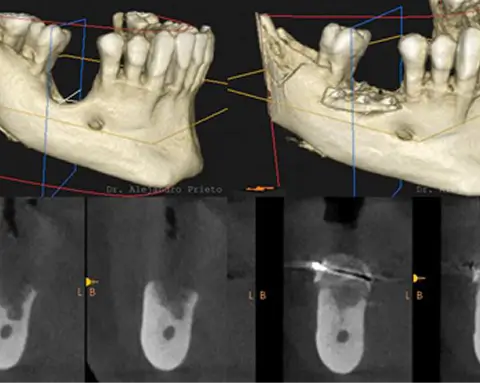

Implantes dentales con tecnología digital avanzada y primeras marcas.

Alejandro Prieto Dental es reconocida por tratar casos de implantes dentales complejos que requieren planificación avanzada y alta experiencia quirúrgica. Se utilizan exclusivamente marcas líderes a nivel mundial y protocolos digitales diseñados para lograr la mayor precisión, estabilidad, funcionalidad y estética natural.

Sí. El Dr. Alejandro Prieto es conocido a nivel internacional por su experiencia en implantología avanzada, incluyendo casos con pérdida ósea severa y situaciones clínicas complejas. Su trabajo se basa en una planificación minuciosa mediante el uso de las útimas técnicas digitales, combinando resultados de alta estética natural. El Dr. Alejandro Prieto recibe pacientes de todo España y del mundo para solucionar casos complejos de implantología.

PicDental: sistema líder de fotogrametría dental digital de alta precisión para implantes, que captura la posición exacta de los implantes y permite prótesis pasivas, ajustadas y altamente predecibles.